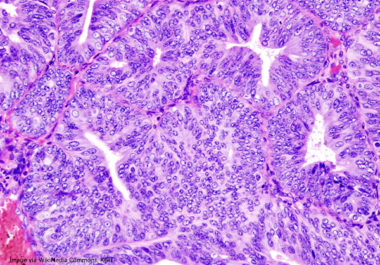

Lorazepam used to relieve stress may cause inflammation that promotes tumor growth and shortens progression-free survival, study says. A medication commonly used to ease the stress caused by cancer diagnosis and treatment may be...